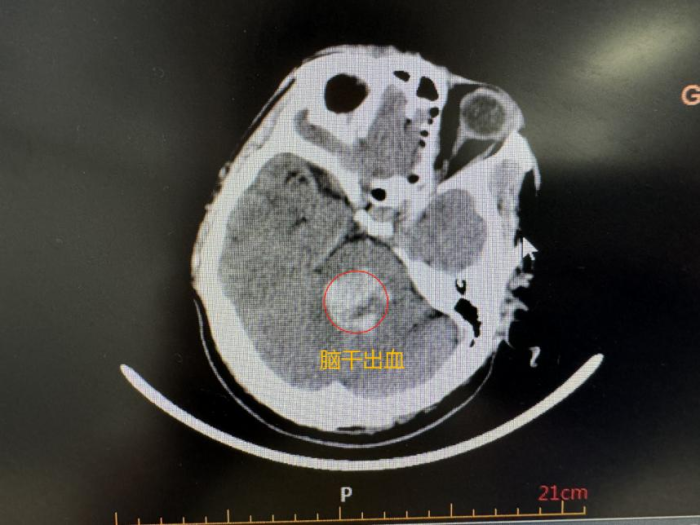

4月9日,56岁男性患者,因突发脑干出血,突发意识障碍伴呕吐,拨打120急救送入贵州医科大学附属白云医院。贵州医科大学附属白云医院立即开启脑卒中“绿色通道”,经MDT团队急会诊后,急诊CT诊断颅脑桥脑出血并破入第四脑室,立即将患者收治神经外科进行手术治疗。因患者病情危急,经过专家团队详细检查和评估,决定采用立体定向技术微创置管引流的方法,精准穿刺脑干血肿部位,引流出陈旧性血性液体。

术前CT诊断:颅脑桥脑出血并破入第四脑室